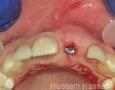

Pictures

Surgery